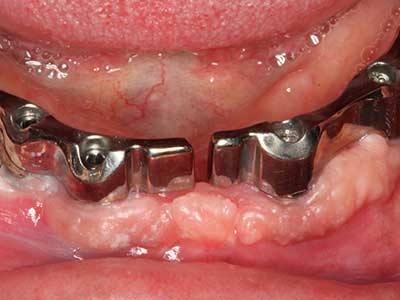

Fig. 13: Adequate irrigation with the 4-mm residual bone width is essential for this 52-year-old patient during the bone splitting.

Fig. 14: Placement of four tapered RSX implants (Bego Implant Systems, Bremen).

Fig. 15: The one-year follow-up x-ray examination shows stable conditions at the bone level.

Fig. 16: The intraoral conditions are also stable with embedding of the implants in keratinized gingiva.